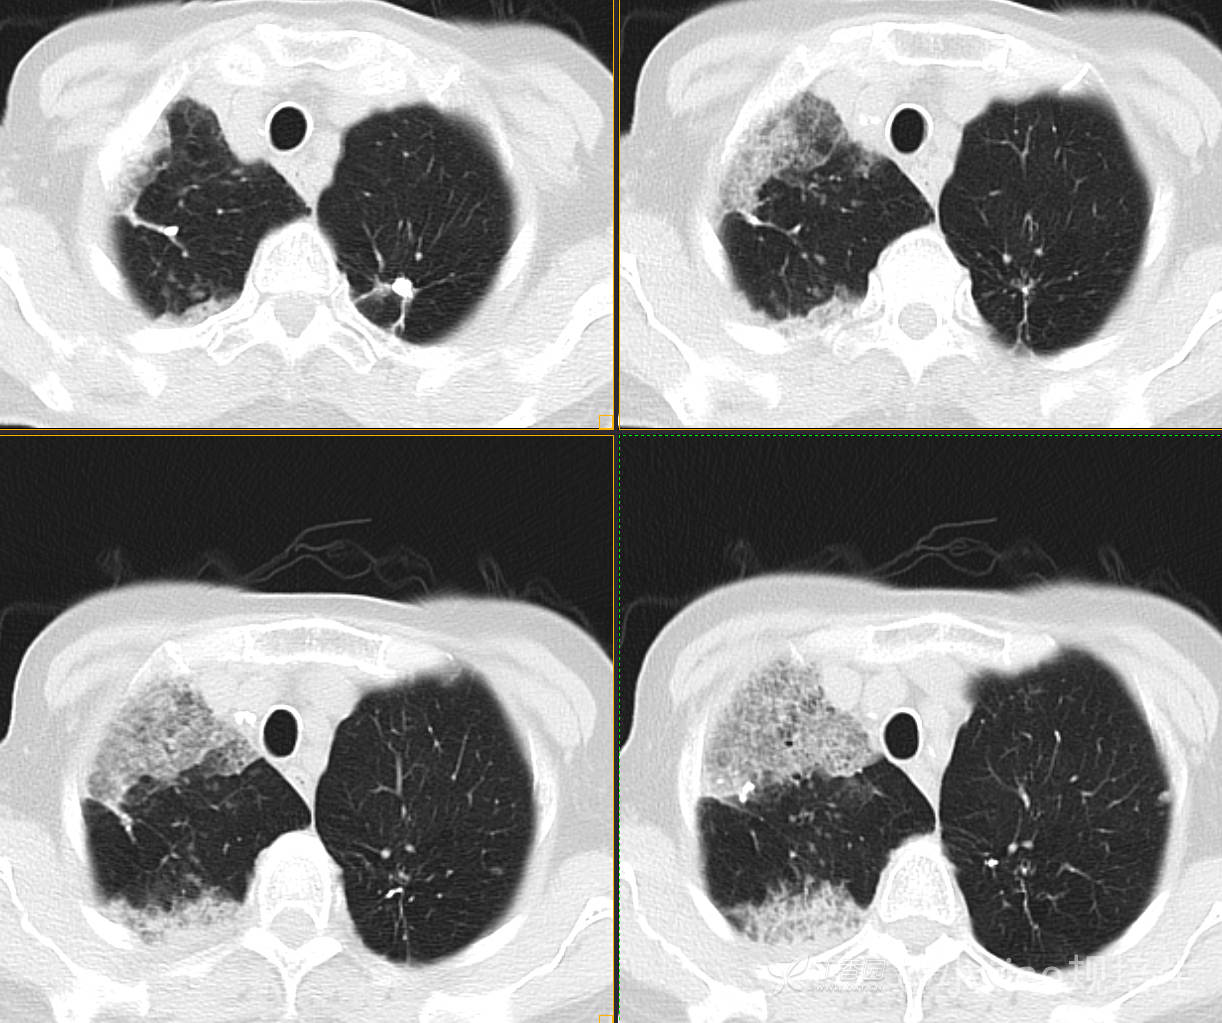

患者,女,89岁

咳嗽,咳痰一月余

肺泡蛋白沉着病 (19)

腺癌 (183)

弥漫性囊性肺病 (9)